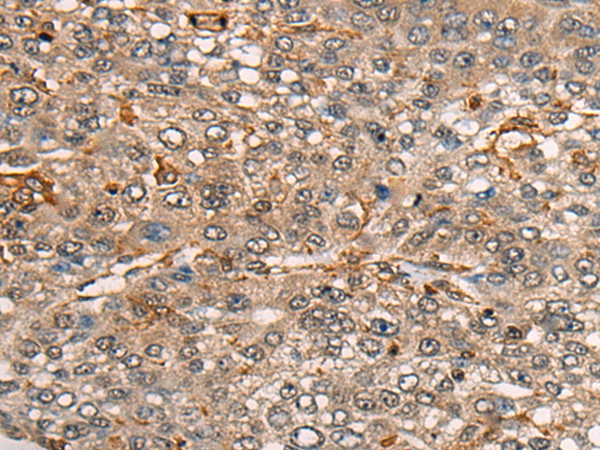

The image on the left is immunohistochemistry of paraffin-embedded Human lung cancer tissue using 46460(CDT1 Antibody) at dilution 1/45, on the right is treated with synthetic peptide. (Original magnification: x200)

The image on the left is immunohistochemistry of paraffin-embedded Human liver cancer tissue using 46460(CDT1 Antibody) at dilution 1/45, on the right is treated with synthetic peptide. (Original magnification: x200)